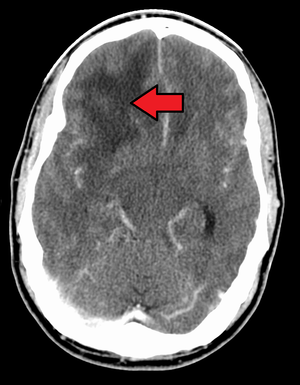

| الطريقة التشخيصية | الأشعة المقطعية، الرنين المغناطسي، الخزعة[1] |

في معظم الحالات الأسباب غير معروفة.[2] ومن عوامل الخطر الشائعة الأمراض الوراثية مثل الورم الليفي العصبي، متلازمة لي-فرومني الخضوع لعلاج إشعاعي سابق.[2][3] يمثل الورم الأرومي الدبقي 15% من أورام المخ.[1] قد يبدأ المرض من خلايا المخ الطبيعية أو يتطور من الإصابة بورم نجمي ليفي.[6] عادة ما يتم التشخيص عن طريق التصوير بالأشعة المقطعية، التصوير بالرنين المغناطيسي والخزعة.[1]